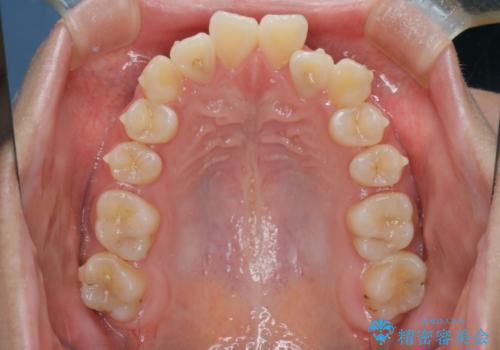

【インビザライン】前歯の凸凹を非抜歯で治療

- 前歯の凸凹を主訴の来院されました。

奥歯を後ろの方に移動させるために矯正用のアンカースクリューを使いながら治療をおこないました。

患者さんの都合により、マウスピースの装着時間が不足したため、途中からワイヤーにて治療を行いました。